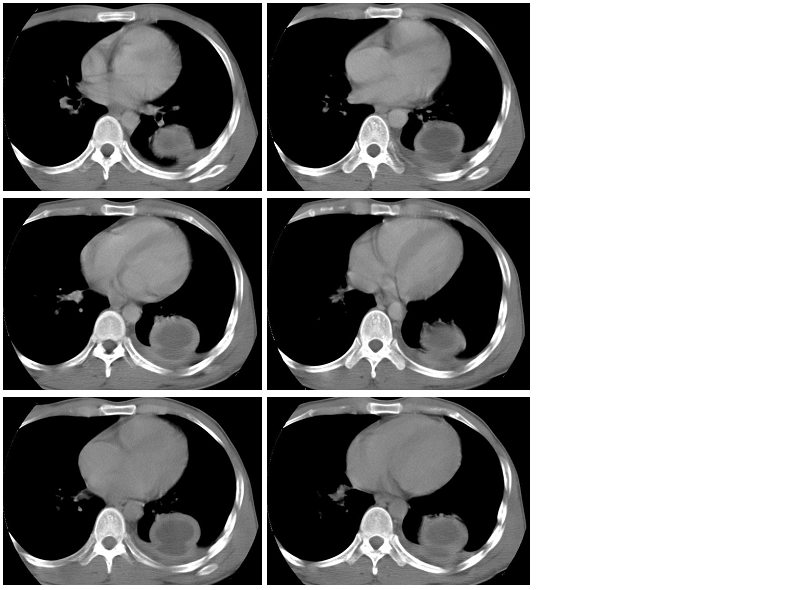

男性,34岁,咳嗽,胸痛一个月,左下肺呼吸音清。分别是肺窗(1-2),纵隔窗(3),增强动脉期(4),平衡期(5),平扫ct值为40-50hu,增强后厚壁达到80-100hu, [/color]

左肺下叶背段肿块影,边缘欠光整,无明显分叶,局部胸膜反应明显,增强扫描明显强化,其内见无强化低密度区,考虑左肺下叶化脓性感染,建议正规抗炎治疗后复查!鉴别诊断:1、结核瘤:环形强化或无强化,周围见卫星灶 2、周围型肺癌:分叶毛刺明显,局部胸膜凹陷征。

类圆形肿块,强化显著,内液化区无强化,考虑左下肺脓肿,左侧少量胸腔积液。

左下肺可见类圆形高密度影,可见双环征,增强后,壁强化明显,内低密度影未见强化,同侧胸腔积液,左下肺脓肿。治疗后复查。